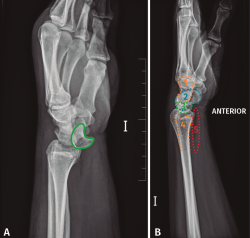

Desde el Servicio de Urgencias se solicita un radiografía anteroposterior y oblicua de mano, muñeca y tercio distal del antebrazo izquierdo. Si observamos detenidamente la radiografía anteroposterior, se observa una alteración en los arcos de Gilula y una posición alterada del semilunar (flexión palmar). Debido a que estas radiografías no son las más adecuadas para el estudio de la muñeca, podría pasar desapercibida la lesión (Figura 1).

Figura 1. Radiografía (A) anteroposterior y (B) radiografía oblicua de mano, muñeca y tercio distal del antebrazo realizadas durante la atención en urgencias inicial. Se observa la fractura de la estiloides radial (flecha). Alteración en los arcos de Gilula (línea). Alteración en la forma del semilunar, en flexión volar (rojo).